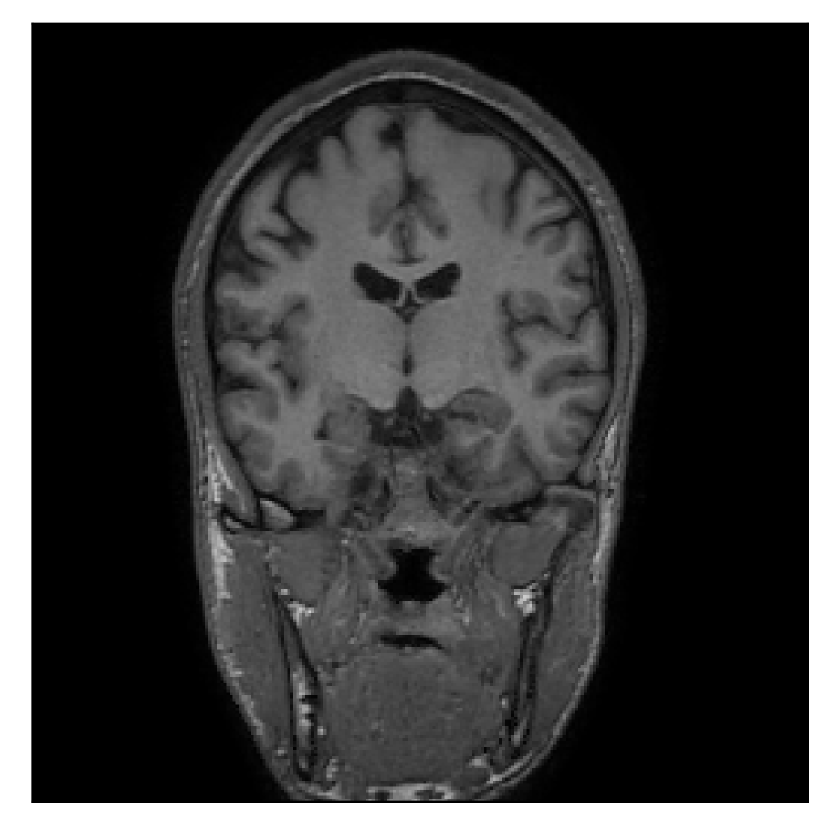

The second experiment is set up similarly to the previous one. We asked volunteer 3 to change position only once during the acquisition phase. We consider, now, a corrupted T2-FLAIR-weighted contrast with a reference T1-weighted contrast (see Table 1). The most important difference with the previous experiment, besides the type of contrast pair considered, is related to the randomized acquisition protocol. In this case, the scanner reconstruction employs a compressed-sensing reconstruction, and is not suited as input for the proposed motion-correction algorithm (see Appendix A). Therefore, for adequate motion correction, we must set up an intermediate step for processing the raw -space data via the SENSE reconstruction.

| Section 3.3, Figure 14 | Sagittal | 24.72 | 28.76 | 0.6762 | 0.7818 |

| Coronal | 25.95 | 29.54 | 0.7238 | 0.8107 | |

| Axial | 25.08 | 29.59 | 0.7263 | 0.8407 | |

| Section 3.3, Figure 14 | T2-FLAIR | Completely corrected | Some blurring | No additional artifacts | Good grey white matter differentiation |

4.3 Experiment 3: scanner reconstruction vs raw k-space data

The results of the two experiments described in Section 3.3 are depicted in Figures 12 and 14. The main difference between the two experiments is related to the input data for the proposed motion-correction algorithm.

In the case of randomized sampling, the scanner reconstruction is not adequate as input data for the proposed motion-correction algorithm, because it employs a compressed-sensing algorithm. We speculate that compressed-sensing reconstructions degrade the information contained in the corrupted volume, and the corrected contrast cannot be effectively recovered by simply removing rigid-motion artifacts (we defer the degraded results when using scanner reconstruction data in Appendix A). However, when the input data is obtained by directly processing the raw -space data via the SENSE reconstruction, the motion-correction scheme is able to successfully remove the motion artifacts (Figure 14).

A significant part of our experimentation was devoted to assess whether the scanner reconstruction (available as DICOM format) can be directly used as input data for the proposed correction method (Section 4.3). We established that the scanner reconstruction is not suitable for this purpose when it is obtained via compressed-sensing algorithms (Appendix A), which is the case for randomized sampling on the 1.5 T Philips Ingenia scanner utilized in this work. In this case, we must resort to the raw -space data and perform an intermediate SENSE reconstruction for effective motion correction.

Sagittal

Coronal

Axial

Axial detail